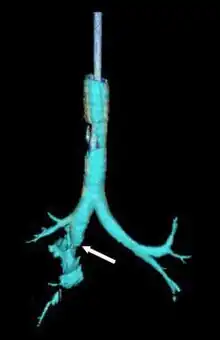

![]() | |

| Reconstruction of the trachea and bronchi with x-ray computed tomography showing disruption of the right main bronchus with abnormal lucency (arrow)[1] | |